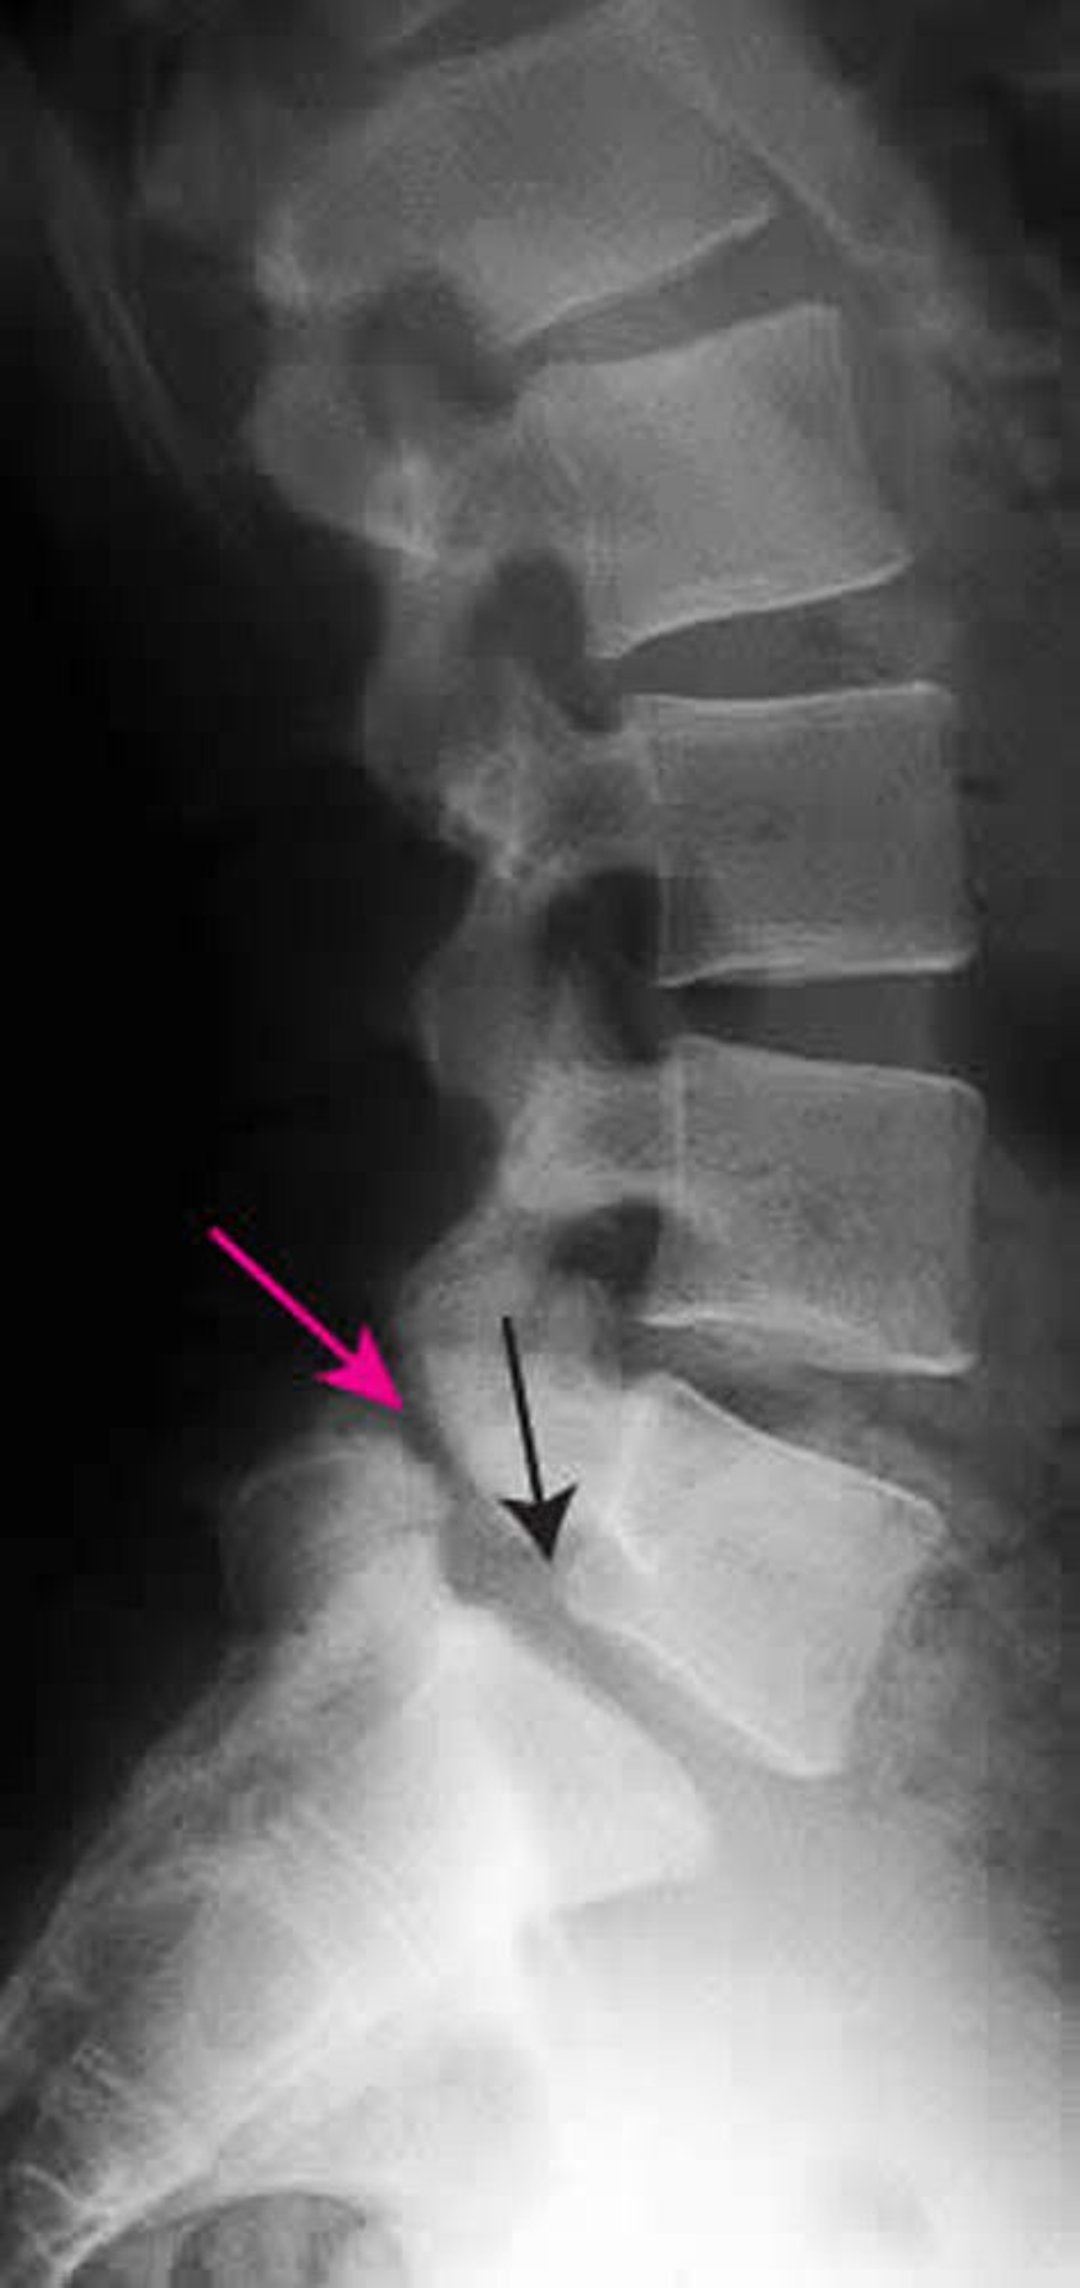

Spondylolisthesis

Diese Röntgenaufnahme zeigt eine Spondylolisthese 1. Grades von L5 auf S1. Der schwarze Pfeil zeigt den hinteren Rand von L5, der anterior zu S1 subluxiert. Der rote Pfeil zeigt auf die Spondylolyse (Defekt in der Pars interarticularis).

ZEPHYR/SCIENCE PHOTO LIBRARY